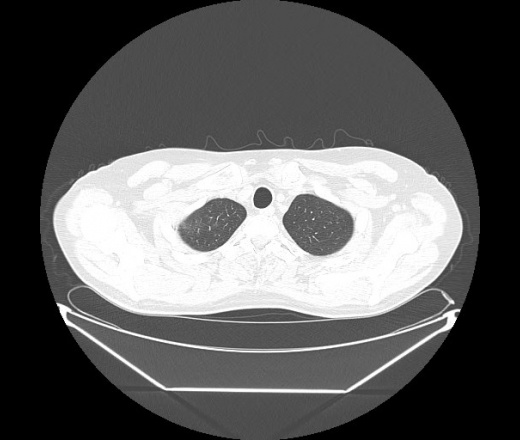

М. 1984 г.р.  Лихорадка 39, кашель , одышка.. и надоевший всем вопрос- "типично ли для ковид?" ( в настоящее время на него обязательно нужно дать ответ в своем протоколе)

На мой взгляд нетипично для ковид: много центрально-расположенных поражений, лобарное поражение нижней доли слева. 50/50

Не типичая картина для ковид.

КТ-признаки двусторонней бактериальной пневмонии.

Все верно, здесь абсолютно нетипичная картина, несмотря на матовое стекло с ретикулярными изменениями, но почему-то  посчитали иначе. Кстати,  "малыша" не заметили)?

Добавил 6 день